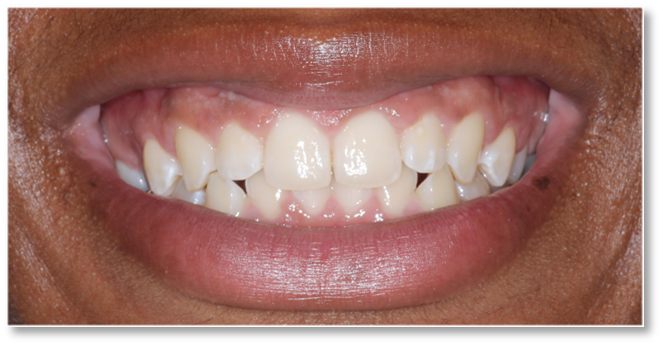

Before and after Periodontal Therapy